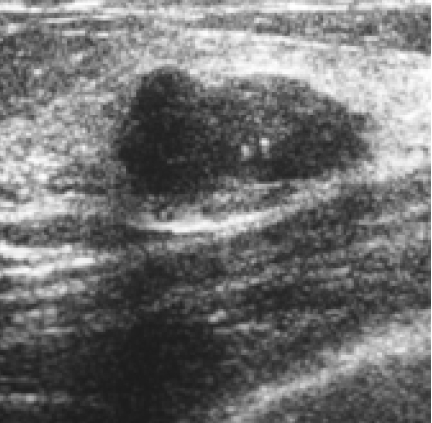

The target dataset was developed from 35 breast ultrasound scans that were segmented by an image-processing expert with extensive experience in breast lesion segmentation (the second author). The images, collected from the Web, are of different dimensions, ranging from to pixels (Figure 3, images resized for sake of illustration). These are the same images used to introduce EFIS originally [1].

Ultrasound images are generally difficult to segment, primarily due to the presence of speckle noise and low level of local contrast. It should be noted that the segmentation of ultrasound actually does require a complete processing chain, (including proper preprocessing and post-processing steps). However, the purpose of using these images was solely to demonstrate that the accuracy of the segmentation can be increased with the application of SC-EFIS.